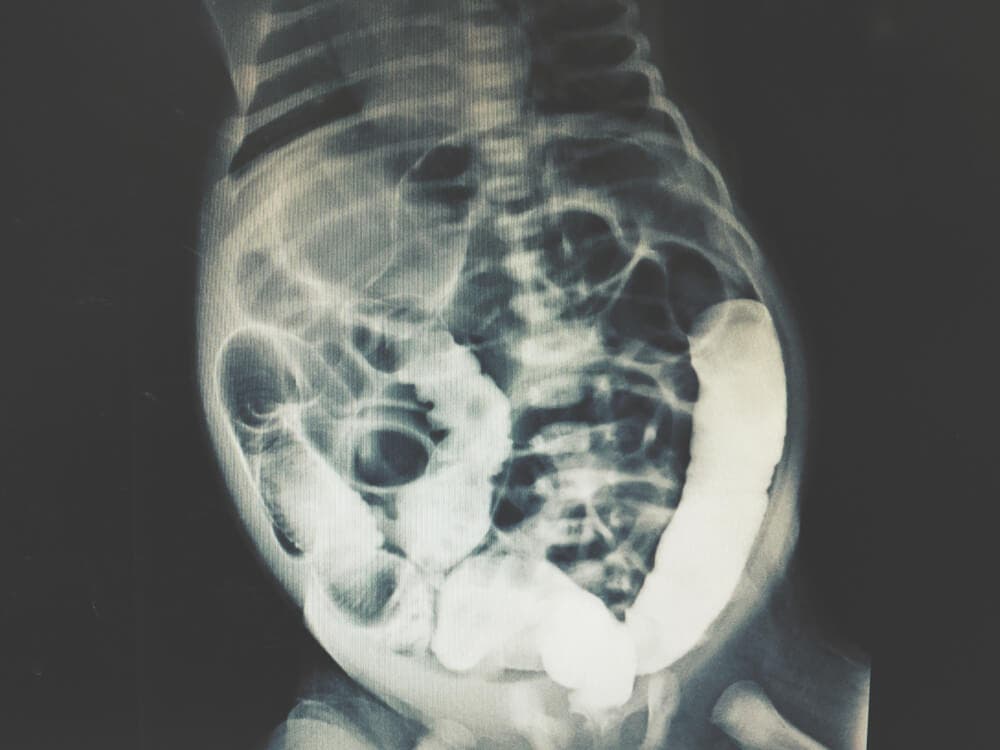

Por norma general, el equipo médico utiliza el término lavado peritoneal diagnóstico para referirse a un procedimiento médico usual. En él, se realiza una exploración física del abdomen que puede ser de gran utilidad a la hora de diagnosticar una patología abdominal grave. También puede aplicarse de forma terapéutica en ciertas condiciones clínicas.

Como indica la evidencia científica, actualmente, se trata de una prueba médica de alta fiabilidad y que produce una mínima cantidad de falsos positivos u otros errores. Además, se emplea junto a otras médicas de diagnóstico por imagen. Es el caso del tomografía axial computarizada (TAC) o resonancia magnética (RM).

De acuerdo a los resultados obtenidos, el grupo de expertos puede determinar la causa de la alteración abdominal. También se pueden llevar a cabo pruebas para obtener imágenes internas de la región abdominal para facilitar el diagnóstico.